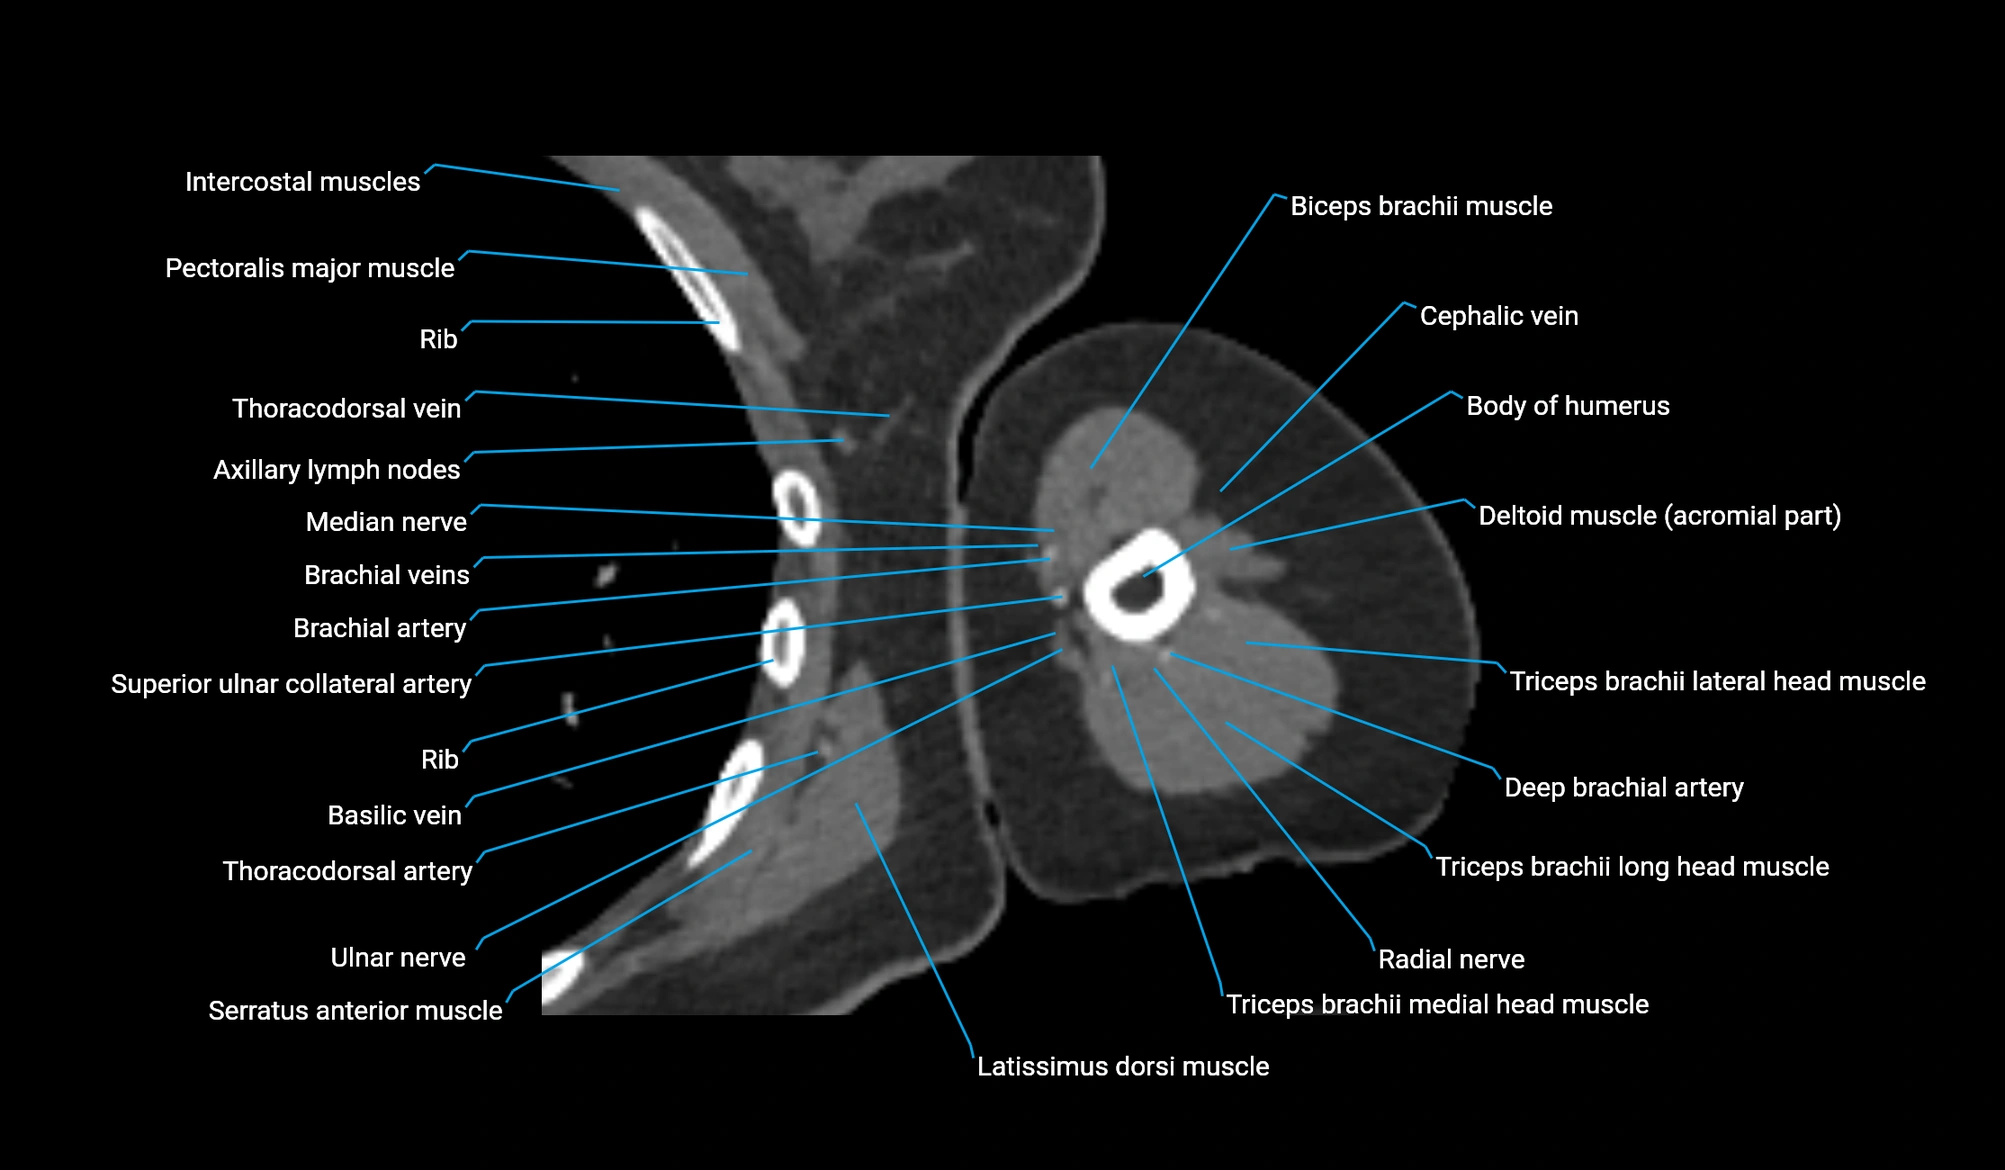

- Basilic vein

- Brachial artery

- Cephalic vein

- Deep brachial artery

- Lateral head of triceps brachii muscle

- Long head of triceps brachii muscle

- Medial head of triceps brachii muscle

- Median nerve

- Pectoralis major muscle

- Radial nerve

- Superior ulnar collateral artery

- Teres major muscle

- Thoracodorsal artery

- Ulnar nerve